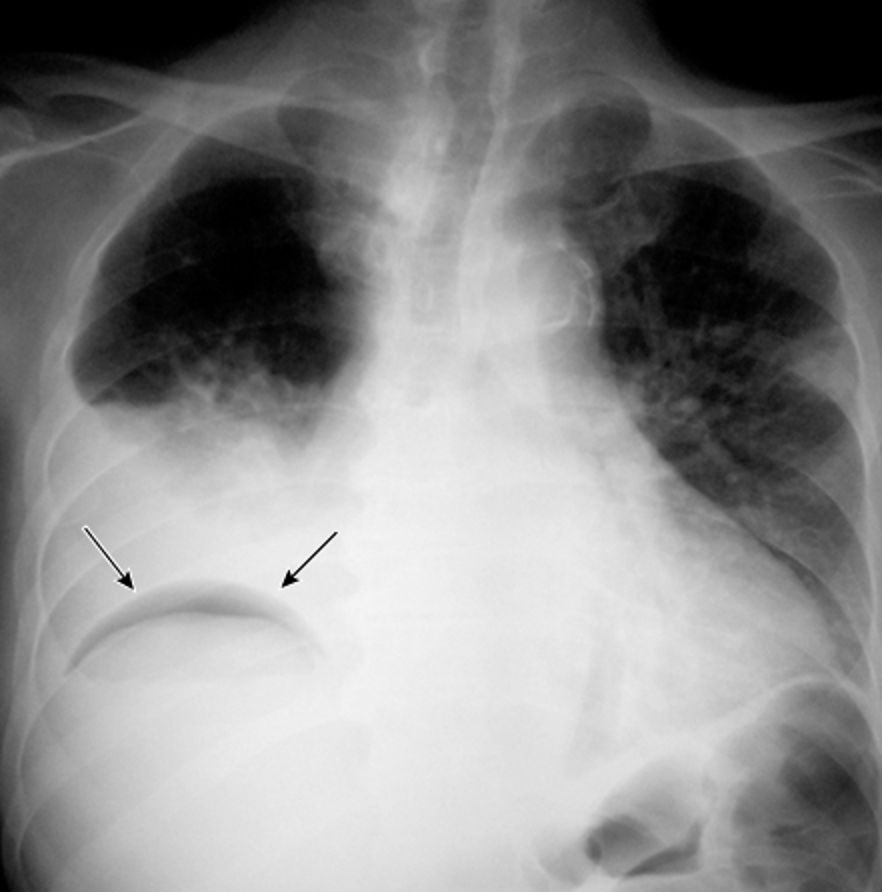

10/ With large pleural effusions, you typically get a contralateral shift of the mediastinum. However, with lung entrapment you will typically see the mediastinum shift ipsilaterally of the effusion or no shift at all. @CritCareMed @PulmCrit @MedEdPGH @gradydoctor